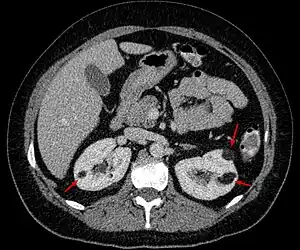

| Angiomyolipoma in both kidneys (arrows) as seen on CT scan. The tumors are hypodense (dark) due to fat content. | |